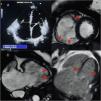

A 62-year-old female patient with no history of cardiovascular disease was admitted to our cardiology ward with acute heart failure. N-terminal proB-type natriuretic peptide was 8789 pg/mL. Echocardiography showed an RV/LV ratio >1, LV global hypokinesia with 30% EF (Figure 3). The computed tomography pulmonary angiogram was normal. CMR revealed regional RV free wall hypokinesia with aneurysms (Figure 3), RVEDV of 179 mL/m2 with 24% RVEF, epicardial LV posterolateral wall LGE, basal mid-septum LGE and RV free wall LGE (Figure 3). The final diagnosis was biventricular arrhythmogenic cardiomyopathy. The management of the patient included angiotensin-converting enzyme inhibitors, beta-blockers, diuretics and ICD implantation. Numerous studies have confirmed a high prevalence of LV involvement among ARVC patients with a range from 61% to 76% of cases.4,5